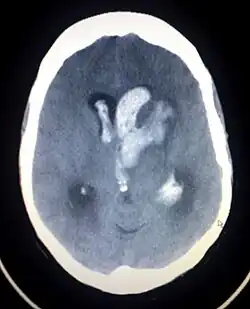

Imaging neuroradiologico

La TC è l'esame di prima istanza da eseguire in corso di ischemia acuta in quanto tecnica rapida, ampiamente disponibile e in grado di fornire tutte le informazioni necessarie: escludere alcuni "stroke mimickers", individuare la presenza di emorragie (differenziando quindi l'ictus ischemico da quello emorragico) e riconoscere i segni precoci di ischemia, che precluderebbero la possibilità di effettuare un trombolitico medico o interventistico.

Nel caso di ictus ischemico o di ictus emorragico con presenza di emorragia subaracnoidea, all'esame TC di base dovrebbe sempre seguire l'esecuzione di uno studio angio-TC: nel primo caso per individuare la presenza di un trombo in un grosso vaso, che può eventualmente essere rimosso, nel secondo caso per ricerca la presenza di malformazioni vascolari che possono aver determinato l'emorragia subaracnoidea (aneurismi, malformazioni artero-venose, fistole durali, ecc.). Gli angiografi di nuova generazione sono in grado di eseguire studi TC direttamente con l'angiografo; l'obiettivo è quello di creare un ambiente in cui il neuroradiologo può eseguire la TC e l'angiografia diagnostiche e l'eventuale trattamento endovascolare senza necessità di trasferimenti del paziente e guadagnando così del tempo prezioso.